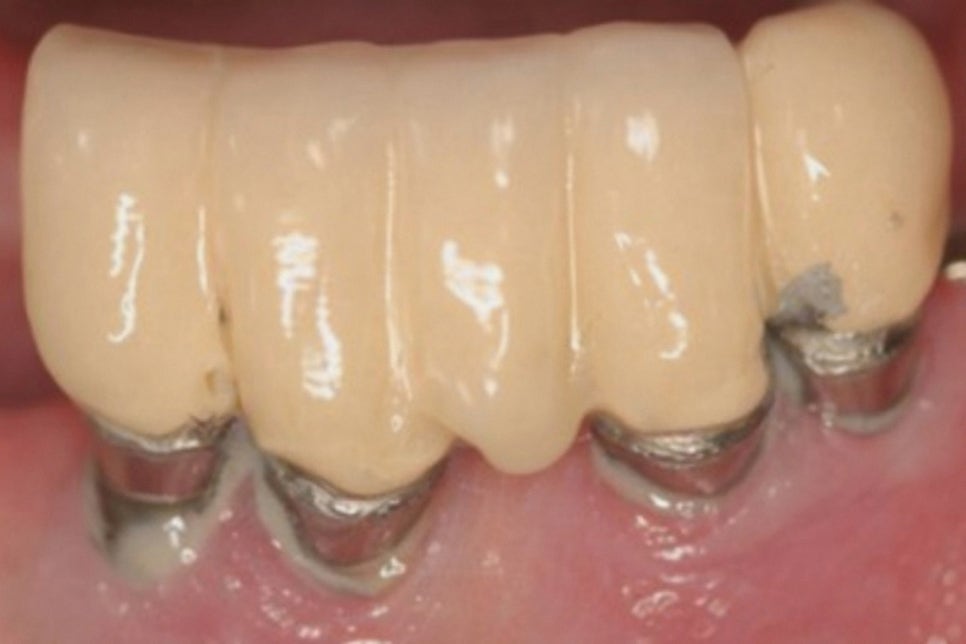

반면 임플란트 는 치조골에 직접 결합되는 구조로

이 과정에서 치주인대가 존재하지 않기 때문에

완충 역할을 하지 못합니다.

이는 저작력을 치조골이 직접적으로

받게 된다는 것을 의미하며,

과도한 압력이 가해지면 픽스처가

손상될 수 있는 위험을 증가시킵니다.

픽스처 주변 조직에 일어나는 염증으로

다음과 같은 원인에 의해 발생합니다.

<불량한 구강 위생>

주변에 쌓인 치태나 플라그는

염증을 일으키는 세균의 서식지가 됩니다.

이를 제대로 제거하지 않으면

세균이 주변 조직에 침투하여

염증을 일으킬 수 있습니다.

따라서 치간칫솔과 같은

구강 위생 용품을 사용해

청결하게 관리를 해주어야 됩니다.